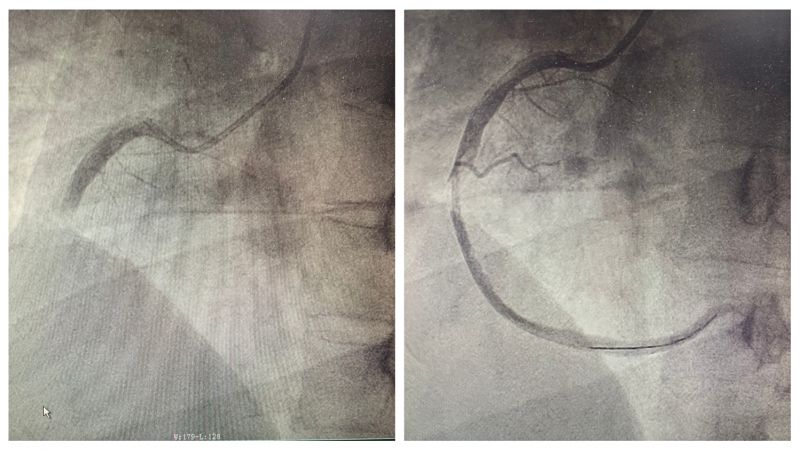

冠脉造影显示患者右冠状动脉急性闭塞,行冠脉介入治疗后血管再通。